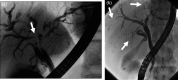

IgG4-related sclerosing cholangitis (IgG4-SC) is a distinct type of cholangitis frequently associated with autoimmune pancreatitis and currently recognized as a biliary manifestation of IgG4-related disease. Although clinical diagnostic criteria of IgG4-SC were established in 2012, differential diagnosis from primary sclerosing cholangitis and cholangiocarcinoma is sometimes difficult. Furthermore, no practical guidelines for IgG4-SC are available. Because the evidence level of most articles retrieved through searching the PubMed, Cochrane Library, and Igaku Chuo Zasshi databases was below C based on the systematic review evaluation system of clinical practice guidelines MINDS 2014, we developed consensus guidelines using the modified Delphi approach. Three committees (a guideline creating committee, an expert panelist committee for rating statements according to the modified Delphi method, and an evaluating committee) were organized. Eighteen clinical questions (CQs) with clinical statements were developed regarding diagnosis (14 CQs) and treatment (4 CQs). Recommendation levels for clinical statements were set using the modified Delphi approach. The guidelines explain methods for accurate diagnosis, and safe and appropriate treatment of IgG4-SC.